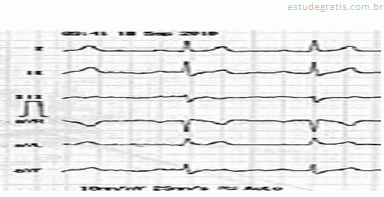

Paciente, sexo masculino, 45 anos de idade, sem patologia

Paciente, sexo masculino, 45 anos de idade, sem patologias prévias, totalmente assintomático, sem histórico familiar positivo para quaisquer patologias cardiovasculares, foi ao médico, pois estava com uma hérnia inguinal. Seu médico solicitou um eletrocardiograma, apresentado em seguida.

Com base nesse caso clínico, e considerando os conhecimentos médicos a ele relacionados, julgue os itens a seguir.

Provavelmente trata-se de síndrome de Brugada tipo III.Comentários